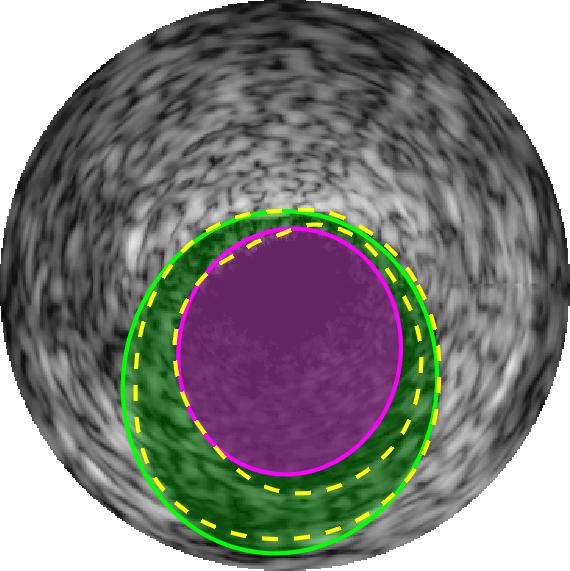

Qualitative evaluations are illustrated in Figure 4 and show the successful segmentation results of the proposed EREL selection strategy for 20 IVUS frames. The lumen areas are highlighted by the magenta colour while the media regions are green. Also, the manually annotated contours for both lumen and media are drawn as yellow dashed lines. As we can see, the chosen frames contain a variety of lumen and media morphologies.